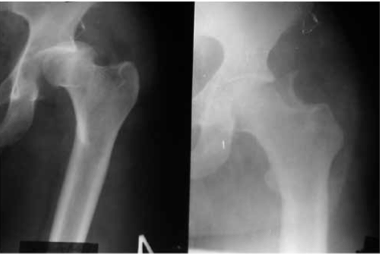

В случае, когда отломок локализуется выше ориентирной линии (рис. 1а, 1б) разрез производится до фасции большой ягодичной мышцы непосредственно по этой линии или несколько выше от проекции основания крестцово-подвздошного сочленения до верхушки большого вертела.

Обзорная рентгенограмма таза. Задне-верхний вывих бедра. Перелом верхнего отдела заднего края вертлужной впадины со смещением отломка.

Обзорная рентгенограмма таза. Вправленный вывих бедра. Перелом верхнего отдела заднего края вертлужной впадины со смещением отломка